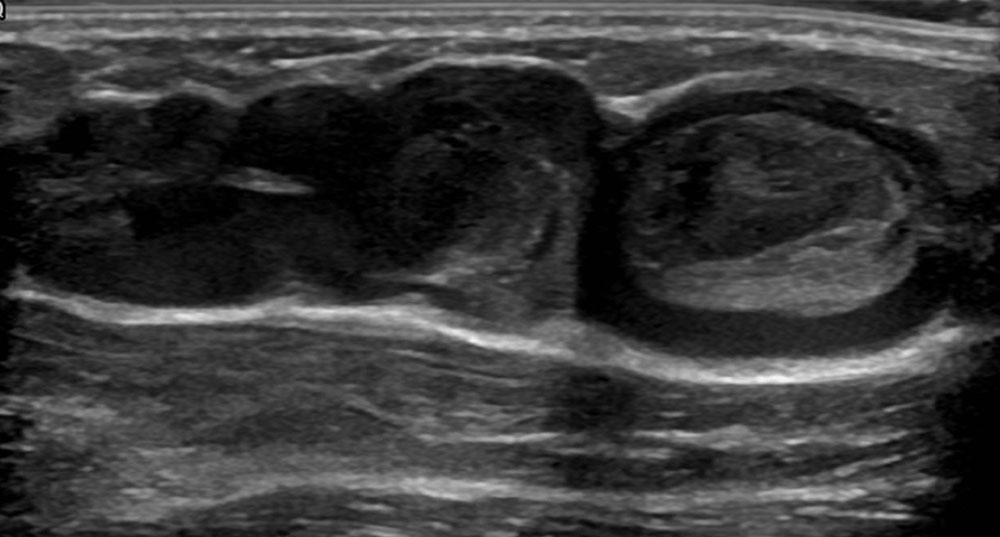

Video: Blood stasis within a venous malformation on ultrasound (B-scan). The very slow blood flow in the dilated vascular spaces of the VM results in the formation of small thrombi, which appear slightly more echogenic (light gray) in the sonogram in contrast to normally anechoic blood (completely black). © Wohlgemuth

The normal organizing degradation of larger local thrombi or thrombophlebitis can lead to collagen deposition, which is palpable as a circumscribed induration over a longer period of time. If the thrombus then still cannot be completely degraded in the venous malformation, calcium deposition and increasing local, shell-like or popcorn-like calcification will occur over time. The final form is the calcified phlebolith as a round calcified lesion 1 cm in size on X-ray images of the venous malformation.